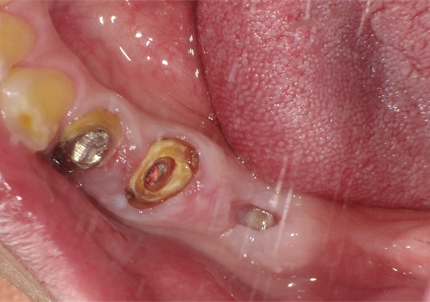

【左下ブリッジ5番6番歯根破折の為要抜歯】

【左下5番ソケットシールドテクニック】

※ 通常、ソケットシールドテクニックは前歯部領域に用いるが小臼歯部でも採用しました

4.左下5番ソケットシールドテクニック